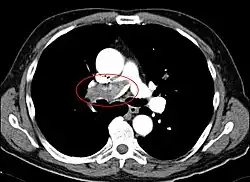

Bei klinischem Verdacht auf eine Lungenembolie, der sich nach sorgfältiger Anamnese und Hilfestellung durch den Wells-Score oder Geneva-Score ergibt, kann die Diagnose am schnellsten mit einer kontrastmittelverstärkten Computertomographie gesichert werden. Im konventionellen Röntgenbild gibt es zwar beschriebene Röntgenzeichen für eine Lungenembolie (Hampton hump, Westermark- und Fleishner-Zeichen), jedoch sind diese eher selten vorhanden und oft nicht eindeutig.